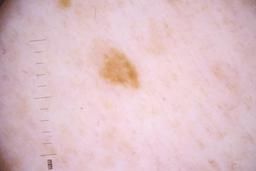

ISIC_4077341

Clinical

| Field | Value |

|---|---|

| acquisition_day | 1 |

| age_approx | 50 |

| anatom_site_1 | Trunk |

| anatom_site_2 | Anterior trunk |

| concomitant_biopsy | False |

| dermoscopic_type | contact non-polarized |

| diagnosis_1 | Benign |

| diagnosis_confirm_type | serial imaging showing no change |

| family_hx_mm | False |

| image_type | dermoscopic |

| lesion_id | IL_9238622 |

| patient_id | IP_1969685 |

| personal_hx_mm | True |

| sex | male |